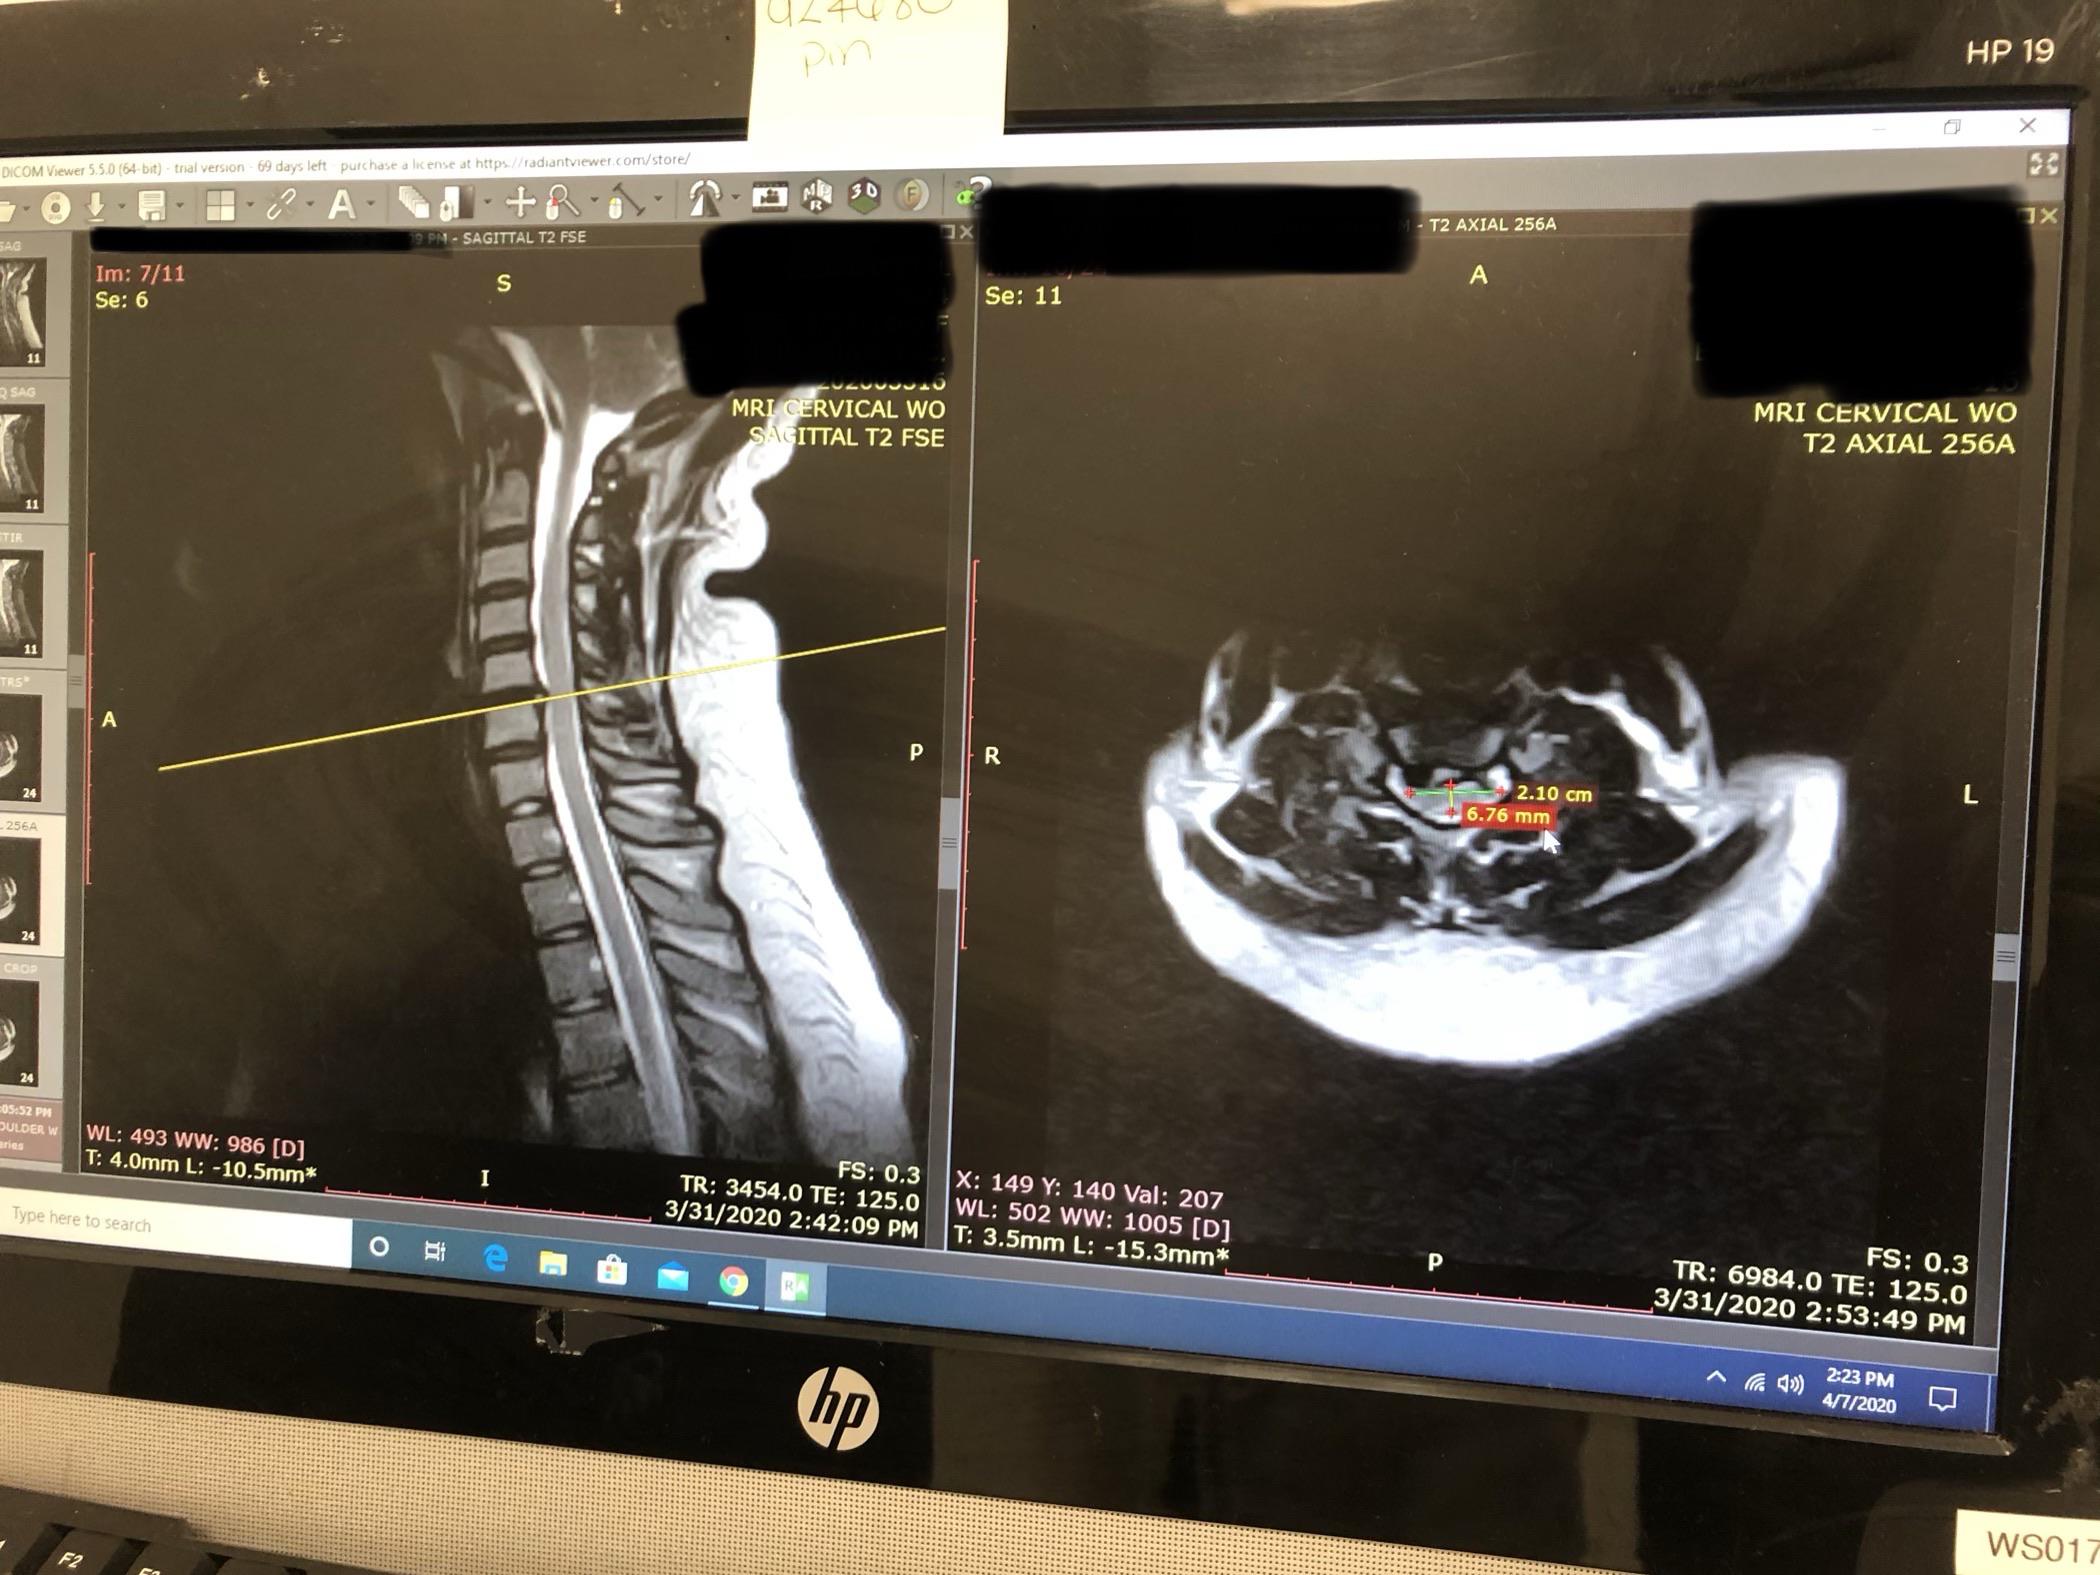

Buying junk yard engines Would you recommend surgery? 26f tboned in car accident : r/spinesurgery

Would you recommend surgery? 26F Tboned in car accident : r/SpineSurgery